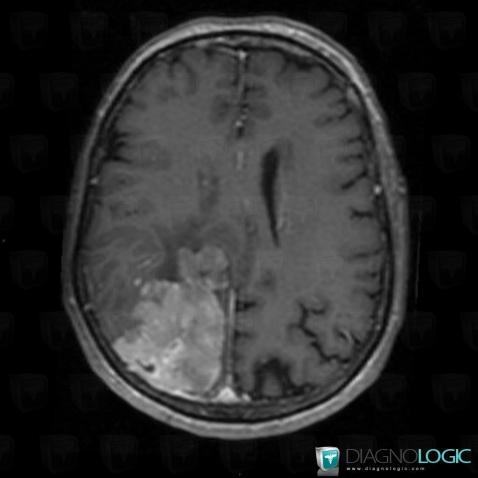

Hémangiopéricytome , Noyaux gris centraux et capsule, Tronc cérébral, Théorique

Voici les informations spécifiques à l'image clé ci dessus:

- Diagnostic Hémangiopéricytome , Localisation(s) Noyaux gris centraux et capsule, comportant les gammes Lésion en hypersignal diffusionTronc cérébral, comportant les gammes Lésion en hypersignal diffusionFosse postérieure, comportant les gammes Lésion en hypersignal diffusion